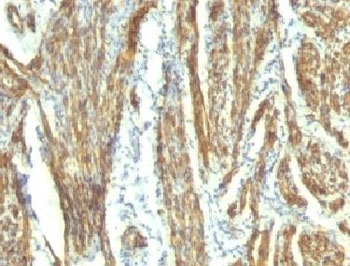

CAD Antibody / Caldesmon CALD1 Tumor Differentiation Marker Antibody. Immunohistochemistry analysis of Caldesmon (CALD1) in human uterus tissue. FFPE human uterus stained with CAD Antibody, clones CALD1/820 and h-CALD, demonstrates strong HRP-DAB brown cytoplasmic staining in smooth muscle cells of the myometrium. The staining highlights interlacing bundles of elongated, spindle-shaped cells consistent with smooth muscle differentiation and contractile cytoskeletal organization. Surrounding stromal and epithelial cells show minimal staining, supporting the role of CALD1 as a tumor differentiation marker associated with smooth muscle lineage and cellular origin.

In tumor systems, CALD1 expression is strongly associated with cells that retain smooth muscle characteristics, making it a valuable indicator of lineage fidelity. Tumors derived from or exhibiting smooth muscle differentiation frequently maintain caldesmon expression, whereas epithelial tumors and poorly differentiated malignancies often show reduced or absent expression. This tumor differentiation marker function provides a molecular basis for distinguishing tumor types based on lineage origin.

In addition to tumor cells, caldesmon is expressed in stromal components such as myofibroblasts, which contribute to tumor architecture and microenvironment remodeling. These cells exhibit contractile features and express CALD1 as part of their cytoskeletal machinery, reinforcing its role as a marker of structurally active cell populations within tumors.